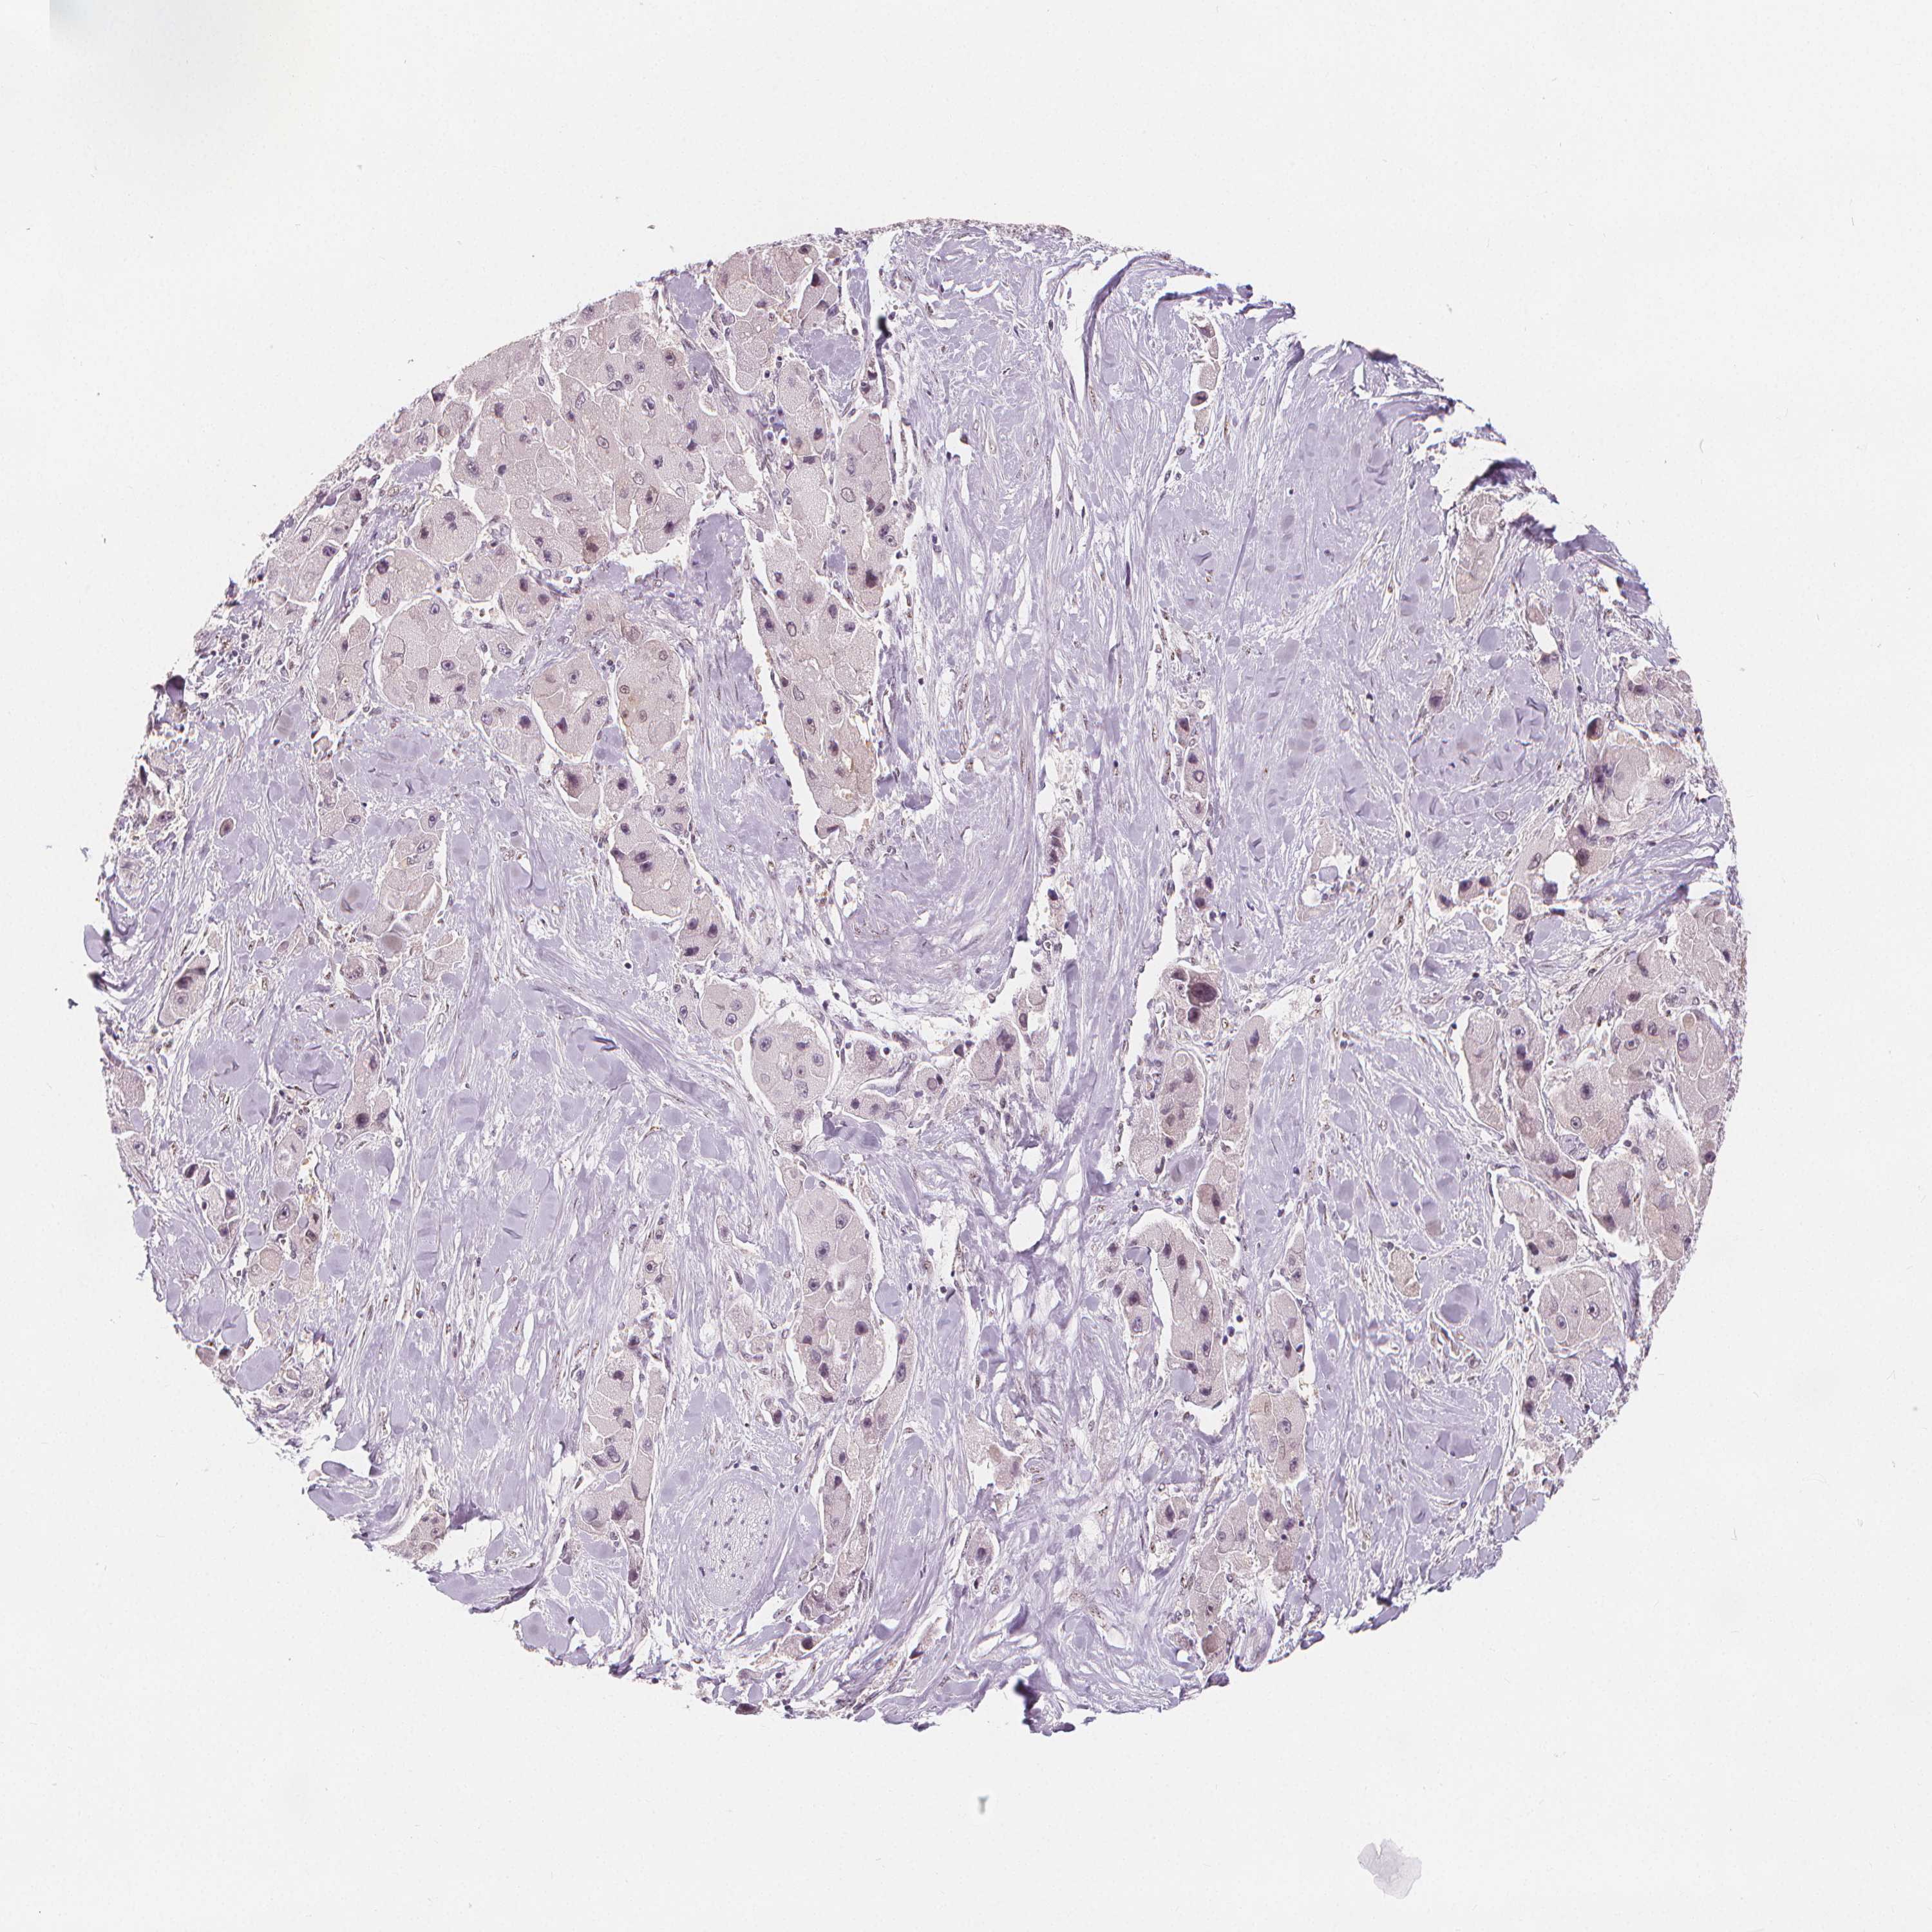

LIVER CANCER - Protein expressioni

A mouse-over function shows sample information and annotation data. Click on an image to view it in a full screen mode. Samples can be filtered based on level of antibody staining by selecting one or several of the following categories: high, medium, low and not detected. The assay and annotation is described here.

Note that samples used for immunohistochemistry by the Human Protein Atlas do not correspond to samples in the TCGA dataset.

Antibody stainingi

Antibody staining in the annotated cell types in the current human tissue is reported as not detected, low, medium, or high, based on conventional immunohistochemistry profiling in selected tissues. This score is based on the combination of the staining intensity and fraction of stained cells.

Each image is clickable and will lead to virtual microscopy that enables deeper exploration of all samples and also displays staining intensity scores, fraction scores and subcellular localization as well as patient and tissue information for each sample.

Antibody HPA036040

Antibody HPA036041

Staining

High

Medium

Low

Not detected

Intensity

Strong

Moderate

Weak

Negative

Quantity

>75%

75%-25%

<25%

None

Location

Nuclear

Cytoplasmic/membranous

Cytoplasmic/membranous,nuclear

Carcinoma, Hepatocellular, NOS

Cholangiocarcinoma